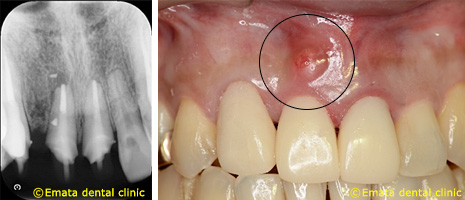

45歳 男性

根もとに膿の袋(黒)ができています。切開やレーザーを照射しても再発します。レントゲンでは矯正をした歯なので、根の先が吸収しています。

CT検査をしました。再根管治療をおこなっても、根が吸収してるので、歯が薄くなり、抜歯に近くなります。

感染源を取り残していると再発の原因になりますので,確実に感染源を取り除くことが大切です。